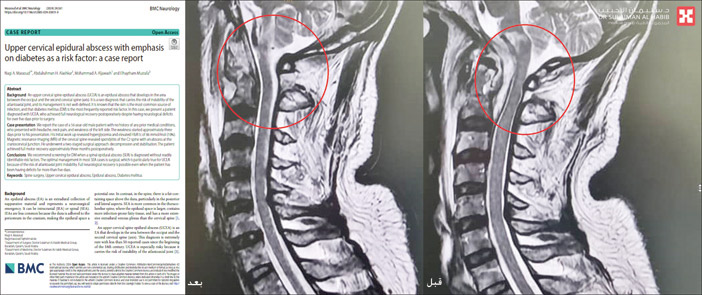

وقال الدكتور ناجي إن المريض وصل إلى الطوارئ وهو يعاني من صعوبة في البلع والتنفس، وتم إدخاله العناية المركزة وإخضاعه لفحوصات طبية دقيقة كشفت عن وجود كتلة صديدية صلبة وأخرى سائلة نادرة الحدوث؛ سببت ضغطاً شديداً على عنق الدماغ والنخاع الشوكي، مع التأثير على مراكز البلع والتنفس، وهو الأمر الذي يفسر الأعراض التي عاني منها المريض خلال الأسابيع الأخيرة، كما أن الأشعة أبانت وجود تهتك بالفقرة الثانية مسبباً التهابات شديدة.

وأوضح الدكتور ناجي أن الفريق الطبي اتخذ القرار بالتدخل الجراحي العاجل عبر عملية نوعية عن طريق الفم (Trans - Oral Approach Through Soft Palat ) ، نظراً لاستحالة إجرائها بالطرق التقليدية، سواء الفتح الجراحي من الأمام أو خلف الرقبة، نظراً لوجود الكتلة الصديدية والسوائل في مستوى مرتفع عن الفقرتين الأولى والثانية مع بداية عظم قعر الدماغ. مشيراً إلى أنه تم إجراء العملية تحت التخدير الكامل واستغرقت نحو 5 ساعات، باستخدام الميكروسكوب «البينترو» المتطور، مع الاستعانة بجهاز مراقبة الأعصاب، وقام الفريق بإزالة الكتلة الصديدية ومعالجة التهتك والالتهابات وتحرير الضغط القائم على الشريان الرئيسي المغذي لعنق الدماغ والنخاع الشوكي.